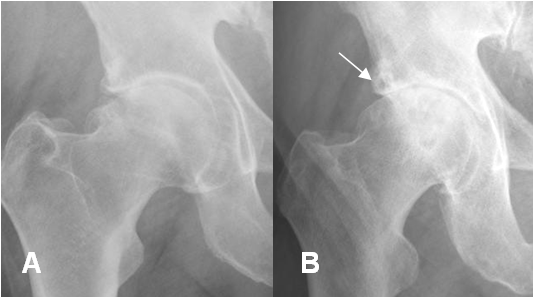

Fig 91. Artropatía degenerativa.

A: Rx AP. Pinzamiento mixto, con disminución del espacio articular, esclerosis y formación de osteofitos.

B: Rx AP. Progresión de los cambios, con aparición de lesión osteocondral en el acetábulo.